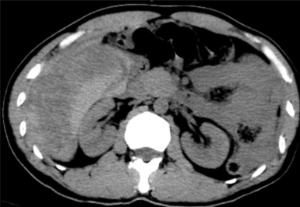

据悉,患者既往有多年乙型肝炎病史,突发右上腹剧烈疼痛入院。患者入院时血压70/40mmHg,心率110次/分,全腹压痛。血常规血红蛋白87g/L,甲胎蛋白>1210 ng/ml。腹部B超检查及CT平扫检查示“肝肿瘤并出血,腹腔积血积液”。